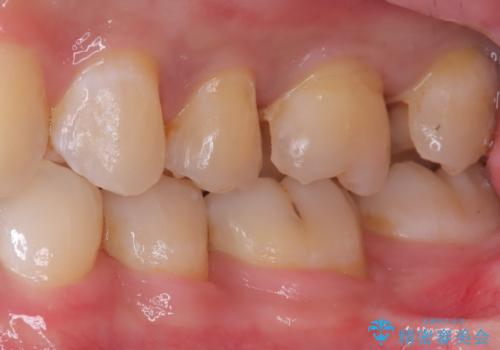

初診でいらした患者様で、口腔内を確認したところ左上6番目と7番目の歯の接する面を中心に両方の歯に虫歯が認められたため、セラミックインレーでの修復治療となりました。

左上6番の歯には元々修復物が入っていましたが、それも一度除去し新たにMOD窩洞のセラミックインレーをセットしました。

左上7番咬合面裂溝の着色部分は今後エアフロー等を使用し落としていく予定です。